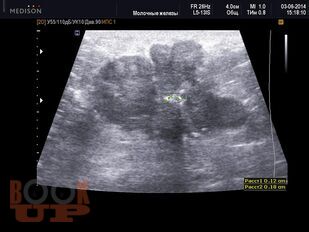

Методические аспекты ультразвукового исследования злокачественных образований молочной железы

В учебном пособии представлены методические подходы к ультразвуковому исследованию молочных желез, определены возможности ультразвукового метода исследования в выявлении и дифференциации вида злокачественных образований молочных желез, проведена оценка его роли и места в диагностическом алгоритме на основании изучения литературных данных и собственных наблюдений.